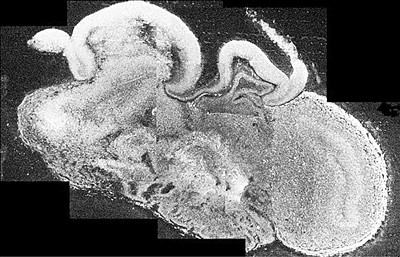

研究人员首先使用干细胞培育出脑细胞,接着让这些脑细胞逐步形成脑组织,最终其与真实的人类大脑一样出现层状的迹象,拥有背皮层、前脑腹侧,甚至包括一个不成熟的视网膜。从结构、功能上看,它都与人类大脑早期发育时的形态酷似。

这个人造大脑直径仅有4毫米左右,但被认为具有很高的科研价值,譬如对头小畸形的治疗研究。该病症属于一种大脑发育障碍,引起病症的原因不一,患者脑子形态正常,但头尾围和脑子缩小,且常伴有脑萎缩和脑损伤症状。研究人员此次发现其细胞分裂低于正常水平,导致脑细胞产生量不足,而这种缺陷可能是诱发该病的原因之一。

科学家们现在于实验室内利用干细胞培植出了一个人类大脑的模型。你可以叫它“微型大脑”,因为这东西直径仅有3毫米到4毫米。但创造者们称其已类似人脑皮层的早期发育区,与真大脑一样呈层状分布——而只有到了人类,大脑皮质的分层次结构才分化得十分清楚,除此之外,从老鼠到人类,所有哺乳动物的神经系统如同按照谁的设计图来造的一样,只不过尺寸上的差别罢了。